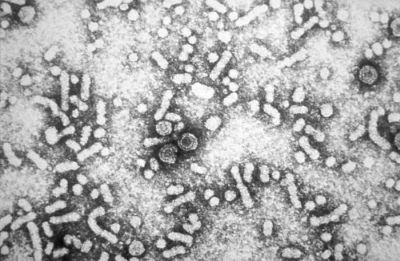

Organisms and infections

Photographs: CDC Public Health Image Library/Wikimedia Commons

Certain viruses and bacteria are associated with an increased incidence of cancer. Infections that raise your risk of the disease include:

- Human papilloma viruses (HPVs)

- Hepatitis B and Hepatitis C viruses

- Human T-cell leukemia/lymphoma virus (HTLV-1)

- Human immunodeficiency virus (HIV)

- Epstein-Barr virus (EBV)

- Human herpes virus 8 (HHV8)

- Helicobacter pylori